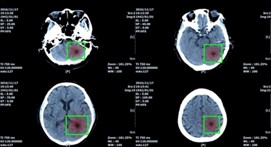

บางครั้งเวลาที่มีรูป X-ray ออกมา ในการตรวจเช็ครูปนั้นจะต้องใช้หมอเฉพาะทางที่มีจำกัด ถ้าเรามี AI คอยช่วย Focus หรือตีกรอบส่วนที่มีปัญหา จะลดเวลาในส่วนนี้มาก รวมถึงอาจจะใช้งานร่วมกับ Image Segmentation ได้ จากรูปด้านล่าง เขาวิเคราะห์เรื่องตำแหน่งของเนื้องอกในสมองครับ